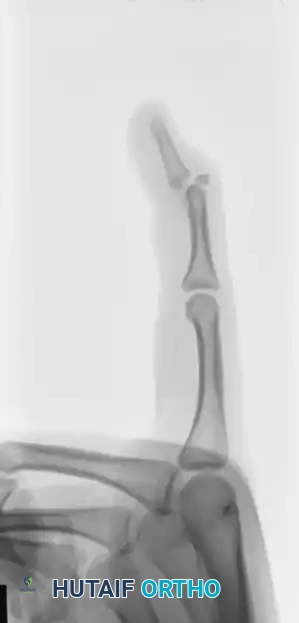

FIGURE 67-64 A and B: Displaced and angulated distal phalangeal fracture associated with a severe nail bed laceration in a 22-year-old patient, demonstrating the classic presentation of a complex open distal phalanx injury.

FIGURE 67-64 C and D: Postoperative radiographic and clinical appearance after precise bone fixation with a K-wire, which provided the necessary stability to permit subsequent realignment and microsurgical repair of the nail bed.